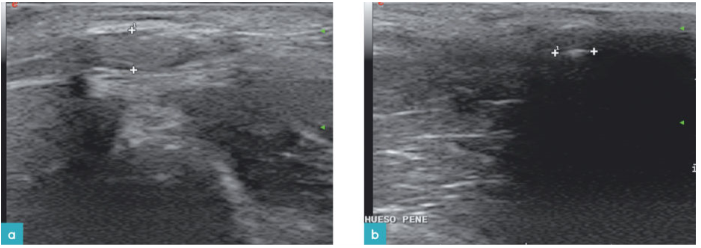

公猫有两个副性腺:前列腺和尿道球腺。前列腺由两部分构成:前列腺体部(前列腺外腺)位于骨盆尿道段头侧的周围;前列腺弥散部位于尿道粘结石(图3)。